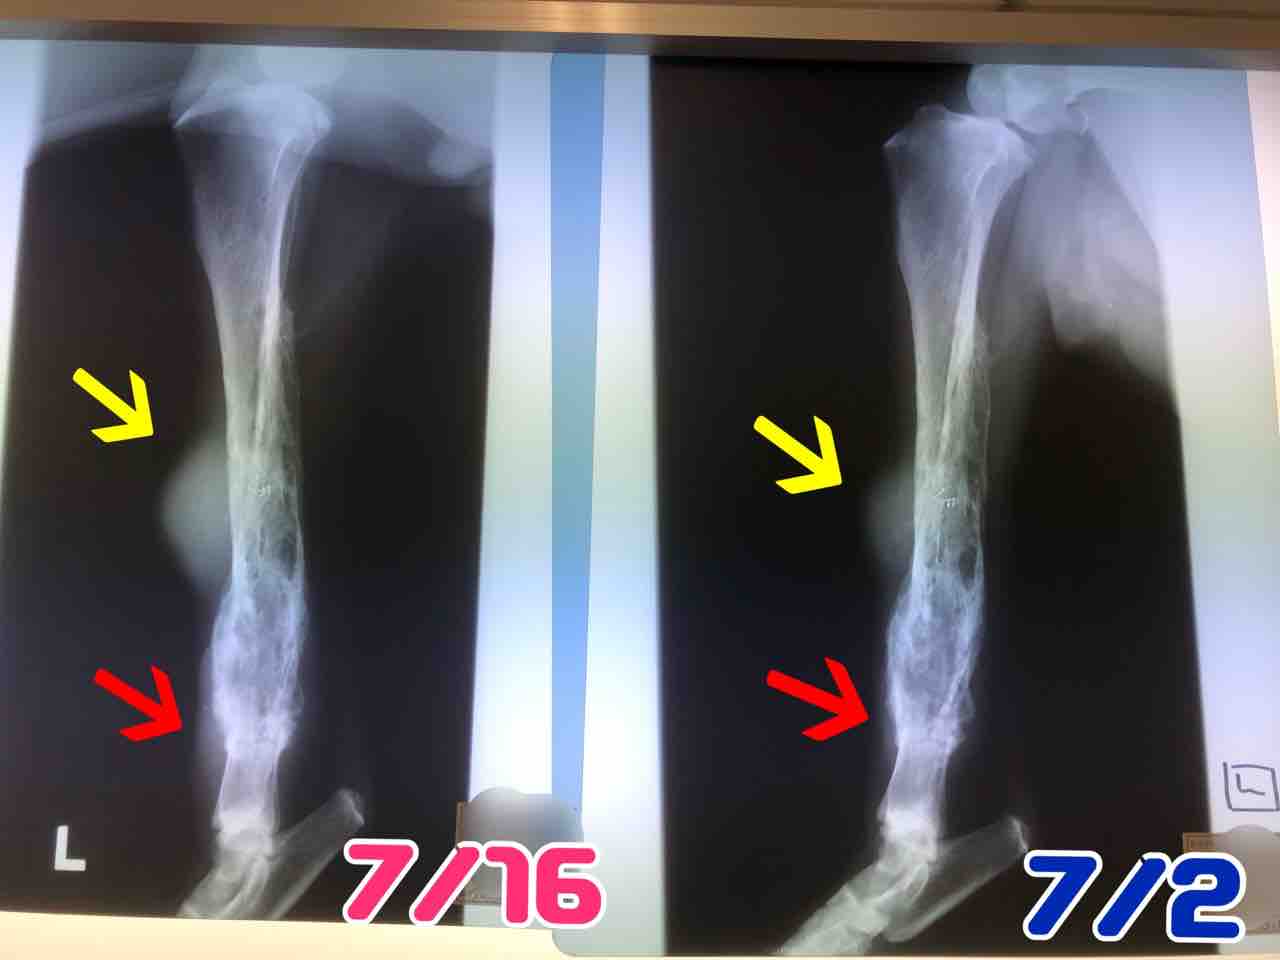

やっぱり、左後ろ脚と右前脚の検査結果は「腫瘍」でした。

細胞検査なので、何腫瘍かははっきりとはわからないけど、普通の骨肉腫とは違い特殊な腫瘍かと。

(腫瘍で骨が溶けてます)

ドンドン大きくなってる後ろ脚の腫瘍をそのままにしておくと、自潰(破裂)するそうです。

右前脚も後ろ左脚も同じように骨が溶けてきているんだけど、後ろは腫瘍が大きくなるのがめちゃくちゃ早い。体調は良いです。

右前脚も後ろ左脚も同じように骨が溶けてきているんだけど、後ろは腫瘍が大きくなるのがめちゃくちゃ早い。